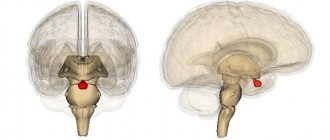

Аденома гипофиза головного мозга (АГГМ) представляет собой опухоль железистой ткани мозгового придатка. Гипофиз –

Общие сведения о патологии Заболевание: встречается нечасто; протекает медленно; редко переходит в злокачественную форму;